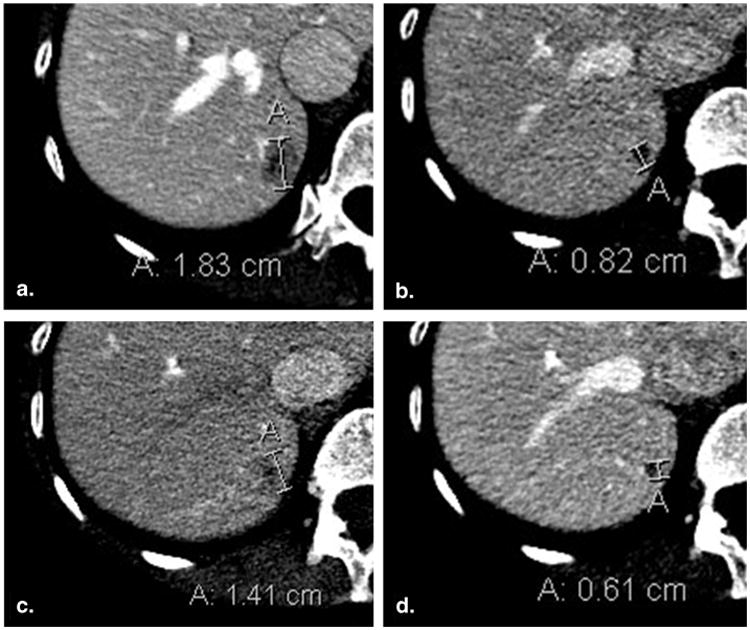

Figure 3.

Lesion remeasurement in a different phase of contrast than baseline (50-year-old female with breast cancer). Baseline contrast-enhanced computed tomography of the abdomen acquired in the portal venous phase (a) demonstrates an 18 mm metastasis in the right hemi-liver. Portal venous phase computed tomography at 8-week (time point #2) follow-up imaging (b) shows that lesion size has decreased to 8 mm. At 16 weeks (time point #3), the lesion was incorrectly evaluated in the arterial phase (c), leading to a measurement of 14 mm and a false assessment of progressive disease. Reevaluation in the portal venous phase (d) yielded a measurement of 6 mm.